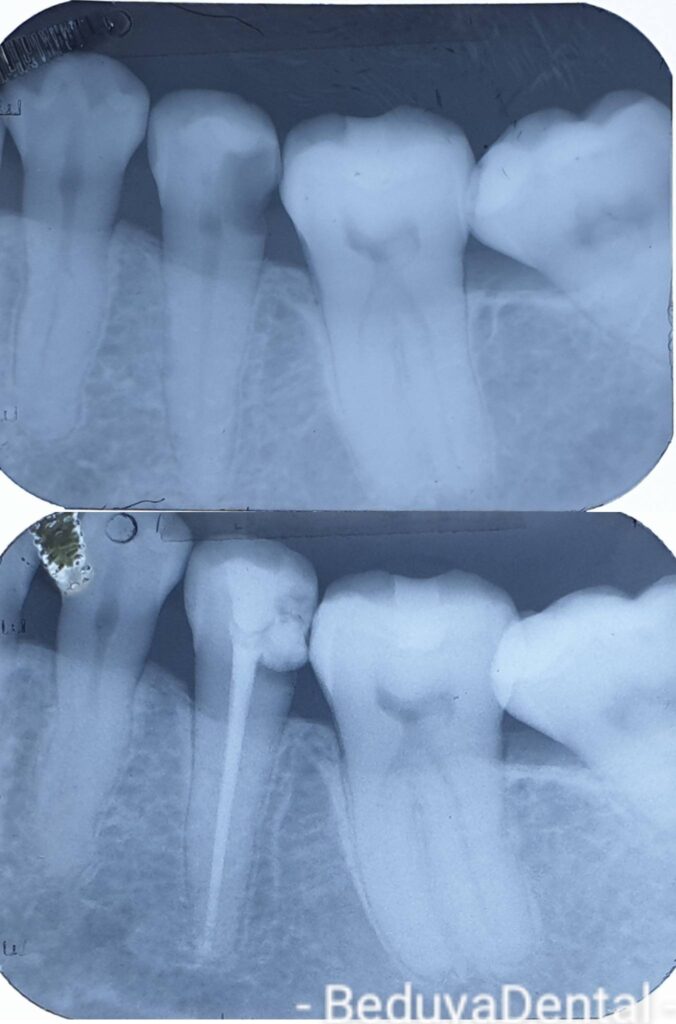

Root Canal Treatment Before & After Photos in Manila

At Beduya Dental in Manila, we specialize in root canal treatment that relieves tooth pain, eliminates infection, and saves your natural teeth from extraction. Our before and after photos showcase real patients who came to us with severe toothache and dental infection — and left with a pain-free, fully restored smile. Root canal therapy has an undeserved reputation, but as you’ll see in our patient gallery, it is a safe, effective, and often painless procedure that preserves your natural tooth for years to come. Browse our results below and see why patients across Manila trust Beduya Dental for their root canal and tooth restoration needs.